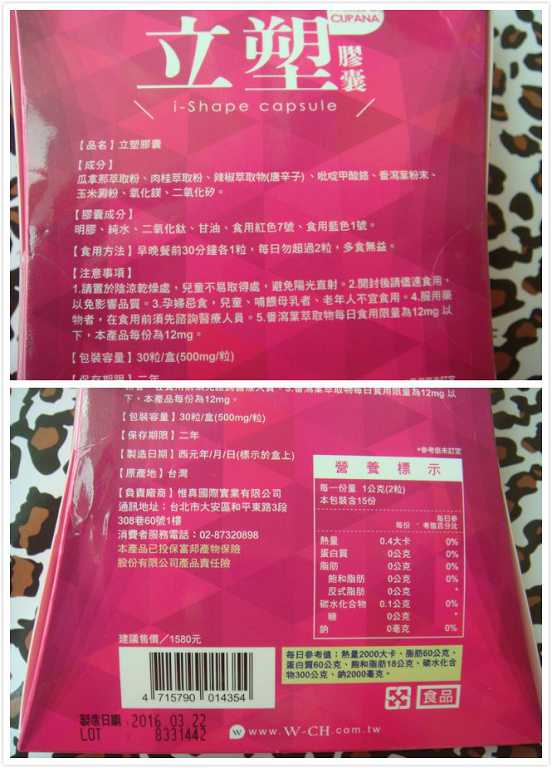

Supercut塑魔纖立塑膠囊的成分有:瓜拿那萃取粉、肉桂萃取粉、辣椒萃取物(唐辛子)、吡啶甲酸鉻、番瀉葉粉末、玉米澱粉、氧化鎂、二氧化矽。

之前上過相關課程,成分表是依照每項成分的多寡來排列順序,排在最前面的就是產品的主要成分!

食用方式:早晚餐前30分鐘各1粒,每日不超過2粒。(多食無益)

番瀉葉萃取物每日食用限量為12mg以下,

鉻與脂肪代謝有關,有助於控制血液中的膽固醇,並有降低血壓的作用,可以預防高血壓,對降低體重也有不錯的效果。